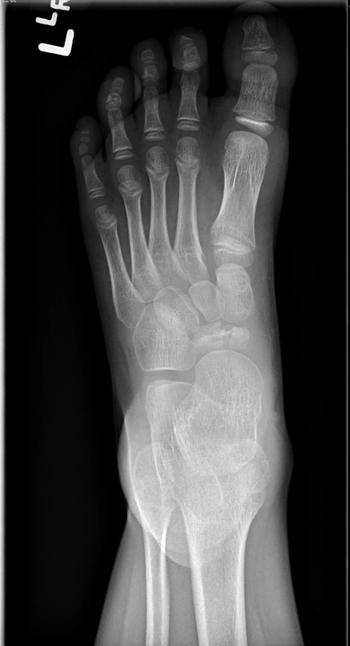

What is your diagnosis for a pediatric patient who presents with findings on a foot radiograph?